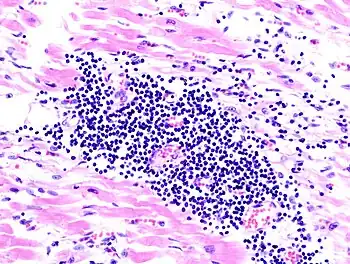

Endomyocardial biopsy specimen with extensive eosinophilic infiltrate involving the endocardium and myocardium (hematoxylin and eosin stain)

The gold standard is the biopsy of the myocardium, in general done in the setting of angiography. A small tissue sample of the endocardium and myocardium is taken and investigated. The cause for the myocarditis can be only diagnosed by a biopsy. Endomyocardial biopsy samples are assessed for histopathology (how the tissue looks like under the microscope: myocardial interstitium may show abundant edema and inflammatory infiltrate, rich in lymphocytes and macrophages. Focal destruction of myocytes explains the myocardial pump failure.[11] In addition samples may be assessed with immunohistochemistry to determine which types of immune cells are involved in the reaction and how they are distributed. Furthermore, PCR and/or RT-PCR may be performed to identify particular viruses. Finally, further diagnostic methods like microRNA assays and gene-expression profile may be performed.